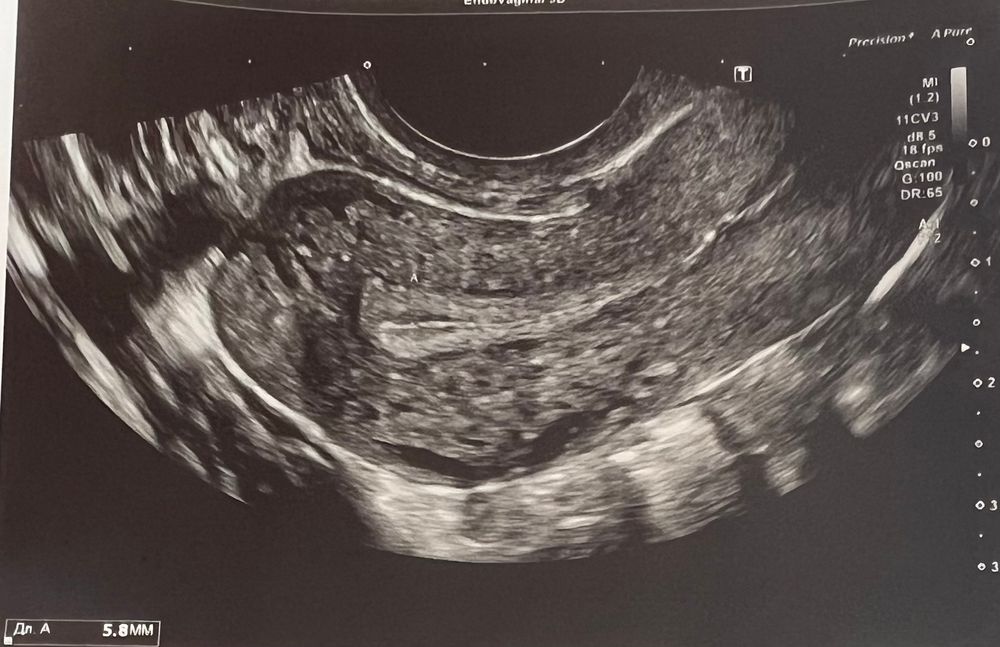

Девочки , может ли из за 1 синехии не расти эндометрий ? Пятых на предмет синехии смотрела , не увидела их. Наблюдалась по УЗИ только у нее с сентября 22г. Недавно врач из Витроклиник увидела синехию ( 2 фото) начинаю думать, что это мешает росту эндометрия(его максимум 6,5 при приеме эстрогенов ). Вообщем в замешательстве я , что делать ?!